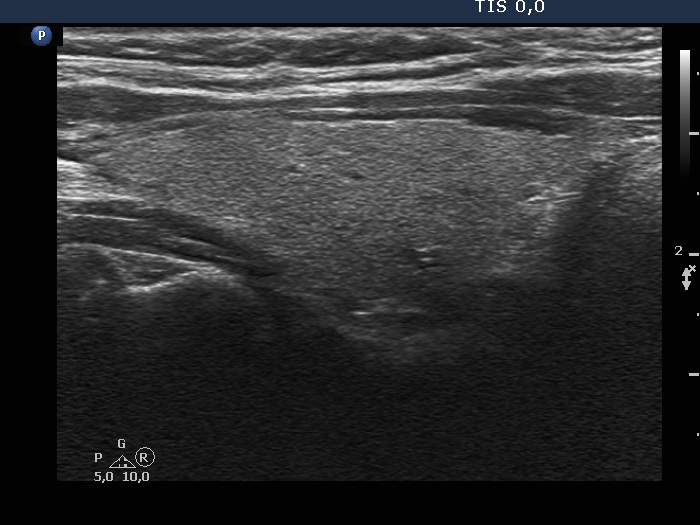

Study on 100 consecutive patients with thyroid nodule - case 042

Three years after the initial examination (ultrasonographic picture 2)

Right lobe, longitudinal view.